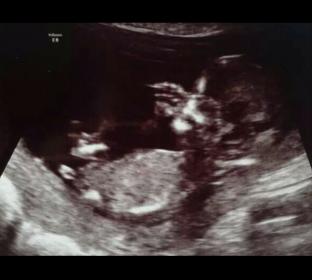

Attachment 21082

Boy

Boy!!

You weren't kidding...pretty obvious boy nub :) Congrats!

I'm going with strong boy.

Looks like boy nub